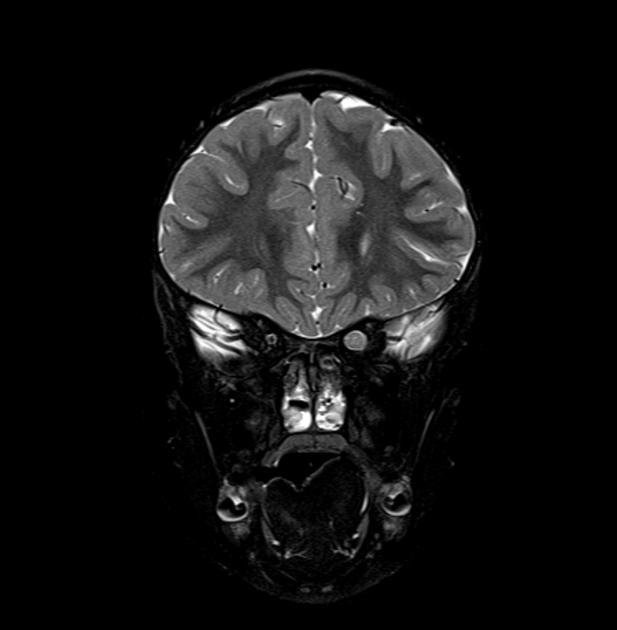

图 4 MRI 检查 T2WI 和 T1WI 强化序列显示,双侧视神经视交叉附近呈明显肿胀,长 T2 异常信号,增强呈明显强化改变

图 7 MRI 检查轴位 T2WI 及 T1WI 强化序列显示双侧视神经肿胀呈长 T2 信号,强化呈明显强化,累及视交叉及颅内脑组织